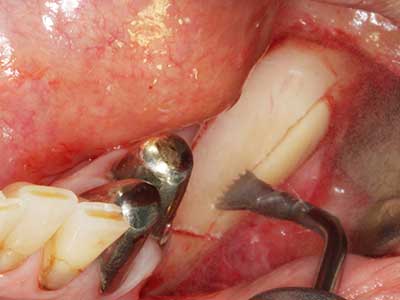

When surgical procedures are performed on bone in the immediate vicinity of sensitive structures such as blood vessels or nerves, rotary instruments pose a significant risk of iatrogenic injury. Piezoelectric devices can be helpful for preparation of bone covers and removal of hard tissue close to nerves, particularly for exposure of nerves after iatrogenic injury but also during nerve lateralization for resective and reconstructive procedures or implant placement (Fig. 17-20). Light contact between the piezotip and the nerve does not generally result in damage but proceeding incautiously with saw-like motions or attachments where a residual bone substrate remains may cause temporary or even permanent nerve damage. However, the risk of damage is considered to be substantially lower than when using saws or milling instruments (Pereira, Gealh et al. 2014).